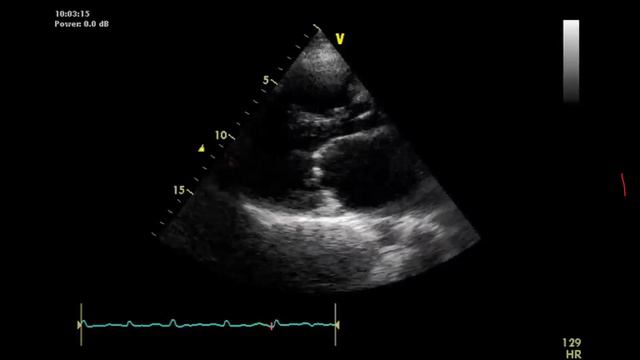

ГиП занятие 7 - болезни митрального клапана Канал: ИПОА ФГБУ НМИЦ ТПМ Минздрава России 24.04.2024 Смотреть

ГиП занятие 8 - диастолический стресс-тест Канал: ИПОА ФГБУ НМИЦ ТПМ Минздрава России 24.04.2024 Смотреть

ГиП занятие 6 - болезни аортального клапана Канал: ИПОА ФГБУ НМИЦ ТПМ Минздрава России 24.04.2024 Смотреть

ГиП занятие 4 - диастолическая дисфункция и СНсФВ Канал: ИПОА ФГБУ НМИЦ ТПМ Минздрава России 24.04.2024 Смотреть

ГиП занятие 3 - типы геометрии ЛЖ и структурное ремоделирование Канал: ИПОА ФГБУ НМИЦ ТПМ Минздрава России 24.04.2024 Смотреть